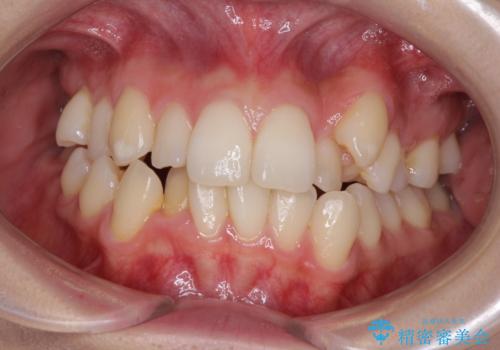

[ ディープバイト ] 深い噛み合わせの改善 マウスピース矯正

![[ ディープバイト ] 深い噛み合わせの改善 マウスピース矯正の症例 治療前](https://seimitsushinbi.jp/wp/wp-content/uploads/2022/03/dc9c092565b160bca6dd53d63f6aeffb-500x350.jpg?v=1646893459)

![[ ディープバイト ] 深い噛み合わせの改善 マウスピース矯正の症例 治療後](https://seimitsushinbi.jp/wp/wp-content/uploads/2022/03/5f1b12b750c3b8c04cdc49e53bc8f89d-500x350.jpg?v=1646893434)